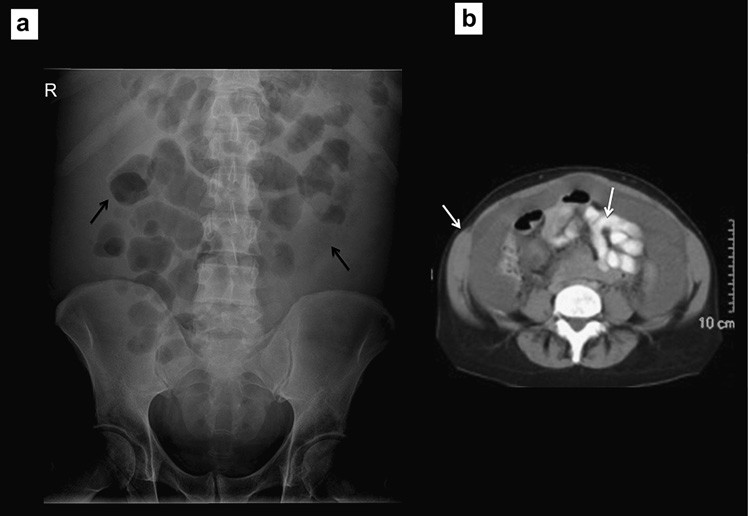

Mặc dù có mức biến đổi rộng về phân bố khí của ruột, nhất là do thành phần dịch trong ruột non biến đổi, sự di lệch hoặc phân bố không điển hình của khí (trong các quai) ruột có thể gợi ý bệnh lý mô trong ổ bụng. Sự di lệch khí ruột do tạng to lên hoặc khối trong ổ bụng, như nang buồng trứng to hoặc khối u thận (Hình 11 và 12). Mặc dù phim X quang không được chỉ định để phát hiện sự di lệch khí ruột khi nghi ngờ tạng to hoặc khối u ổ bụng, dấu hiệu di lệch được phát hiện khi tìm kiếm các triệu chứng khác của ổ bụng.

Hình 11. Di lệch các quai ruột (a) Phình động mạch chủ bụng gây di lệch đại tràng về bên trái. (b) Lách to đẩy các quai ruột sang phải và xuống phần dưới của ổ bụng.

Hình 12. Di lệch các quai ruột (a) Một khối lớn từ tiểu khung đẩy các quai ruột lên phần trên của ổ bụng. (b) CT xác định khối u nang rất lớn của buồng trứng (c, d) Gan, lách to đẩy các quai ruột xuống phần dưới của ổ bụng.

Cổ chướng

Sự hiện diện một lượng dịch lớn trong ổ bụng gây di lệch và các quai ruột tập trung lại hoặc “bập bềnh” ở giữa ổ bụng. Hình ảnh này tạo nên mẫu hình cổ điển trên phim X quang bụng (lưu ý: chụp X quang bụng ở phương Tây gồm 2 phim X quang bụng tư thế nằm ngửa và ngực đứng hoặc ngồi). Trước tình trạng cổ chướng, thường siêu âm và chụp cắt lớp vi tính được yêu cầu để xác định nguyên nhân, thường là bệnh lý gan hoặc ác tính (Hình 13).

Hình 13. Di lệch các quai ruột (a) Các quai ruột bị đẩy vào trung tâm, khẩu kính còn bình thường. (b) CT xác định rất nhiều dịch ổ bụng.